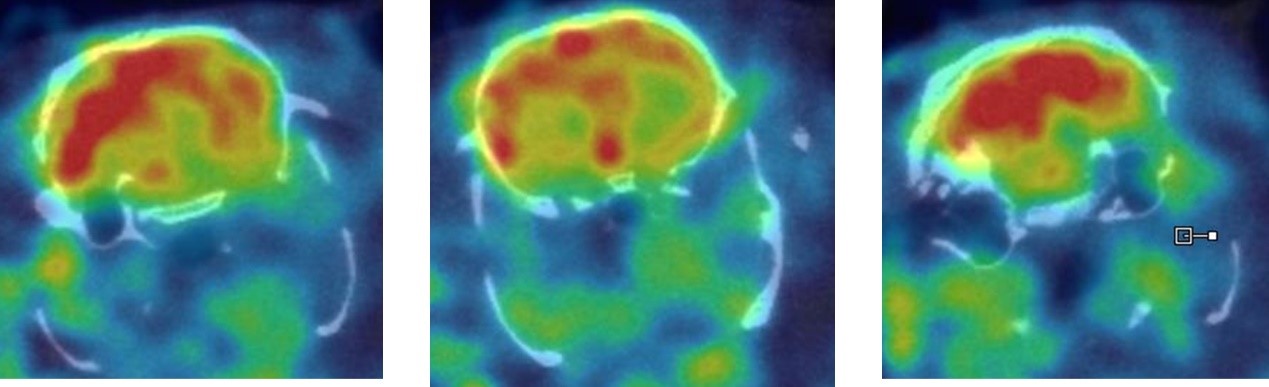

1、神經(jīng)系統(tǒng)SPECT成像

大鼠腦部SPECT成像:99mTc-HMPAO:腦血流灌注顯像劑,用于腦血管疾病,腦外傷,癲癇,癡呆癥,腦死亡的診斷;用于精神疾病的腦功能及正常腦生理功能活動的研究。進(jìn)入腦組織的99mTc-HMPAO構(gòu)型改變而轉(zhuǎn)變成水溶性化合物,無法再次通過血腦屏障而滯留在細(xì)胞內(nèi),因此能在腦內(nèi)長時間滯留。120 MBq,30 min uptake,30 min SPECT。